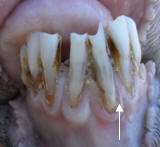

L’analyse des résultats de la mensuration de la hauteur des pinces montre la présence d’écarts, révélés par le coefficient de variation au sein de chaque tranche d’âge. Cet écart augmente avec l’âge des animaux (Tableau 1). Nous avons considéré qu’une pince était longue lorsque la hauteur de sa couronne était >15 mm (Morris et al 1985). L’allongement des pinces est observé dès l’âge de 22 mois (Tableau 1 ; Figure 3) ; ainsi, nous avons répertorié 119 moutons avec des pinces allongées. Tous les animaux présentant ce caractère ont montré une protrusion d’incisives, définie comme une malocclusion dentaire (Figure 4). L’incidence de cette anomalie est très élevée, avec 55 % de l’effectif total. Cependant, dans peu de cas il s’agit de prognathisme ou de brachygnathisme sévères.

Figure 4. Malocclusion dentaire due à la protrusion  des incisives. (A. Vue frontale B. Vue latérale)  |

Chez les moutons présentant de la protrusion (malocclusion), les incisives s’allongent de manière exagérée (Figure 7a) (longueur des pinces > 20 mm chez 30 sujets, soit 14 % de l’effectif total) et souvent l’usure se limite aux pinces. Au-delà de 40 mois, la détermination de l’âge devient difficile en raison de l’absence d’usure régulière des incisives. De surcroit, les anomalies sont très fréquentes. Il s’agit généralement de phénomènes d’usures irrégulières (Figure 7b), notamment la fréquence de l’érosion frontale des pinces (Figure 7: c, d, e), due au broutage de l’herbe à même le sol et à l’ingestion de terre ; du déchaussement, dû à la rétraction de la gencive (Figure 7f) ; de la mobilité et la chute des incisives (mâchoire brisée) (Figure 7 : g, h, i). Par ailleurs, des cas isolés de défauts de moindre importance ont été observés, comme la fissure et la fracture dentaire ; la rotation et la torsion de l’incisive (Figure 7 : j, k, l).

La malocclusion dentaire due à la protrusion des incisives est très fréquente dans les élevages étudiés. Ridler et West (2010) dans leur revue affirment que ce type d’anomalie peut-être largement répandu à l’échelle du troupeau. Par ailleurs, tous les cas de protrusion répertoriés sont accompagnés d’allongement d’incisives. Selon Aichisson et Spence (1984), ces deux problèmes sont étroitement liés.

D’autre part, la malocclusion serait étroitement liée aux différentes anomalies dentaires, comme l’érosion irrégulière ou l’absence d’usure (Aitchinson et Spence 1984 ; Morris et al 1985), la déformation et la courbure (Ridler et West 2010), la fragilité, la mobilité et la chute des incisives, engendrant une mâchoire brisée (McGregor 2011). La protrusion est accentuée par les forces de tiraillement subies par les incisives lorsque les moutons arrachent l’herbe au pâturage (Aitchison et Spence 1984 ; McGregor 2011). De plus, l’allongement des incisives est exagéré par le déchaussement du revêtement gingival, découvrant le collet de la dent, en raison de la contraction de la gencive (Morris et al 1985 ; Ridler et West 2010). Ainsi, ces phénomènes associés favoriseraient le déracinement et la chute de la dent.